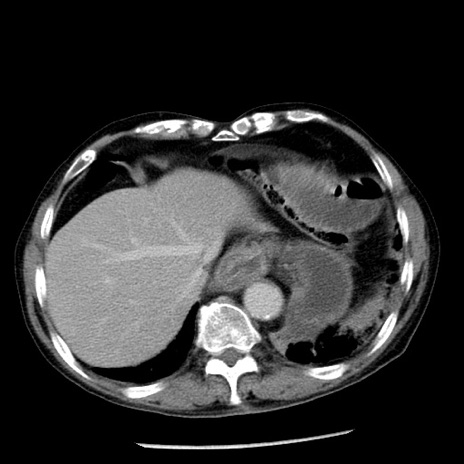

症例26(横断像)

【症例】80歳代男性

【主訴】嘔吐

【現病歴】昨晩2回嘔吐あり、今朝になっても嘔吐あり。来院。

【既往歴】胃潰瘍

【身体所見】意識清明、BT 37.6℃、BP 166/95mmHg、HR 100bpm、SpO2 97%、腹部:平坦・軟、腸蠕動音聴取良好、圧痛なし。

【データ】WBC 21900、CRP 1.46